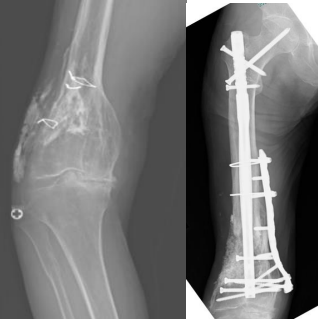

当センターで手術を施行した症例

2.上腕骨骨幹部骨折後偽関節:Masquelet法による骨接合術